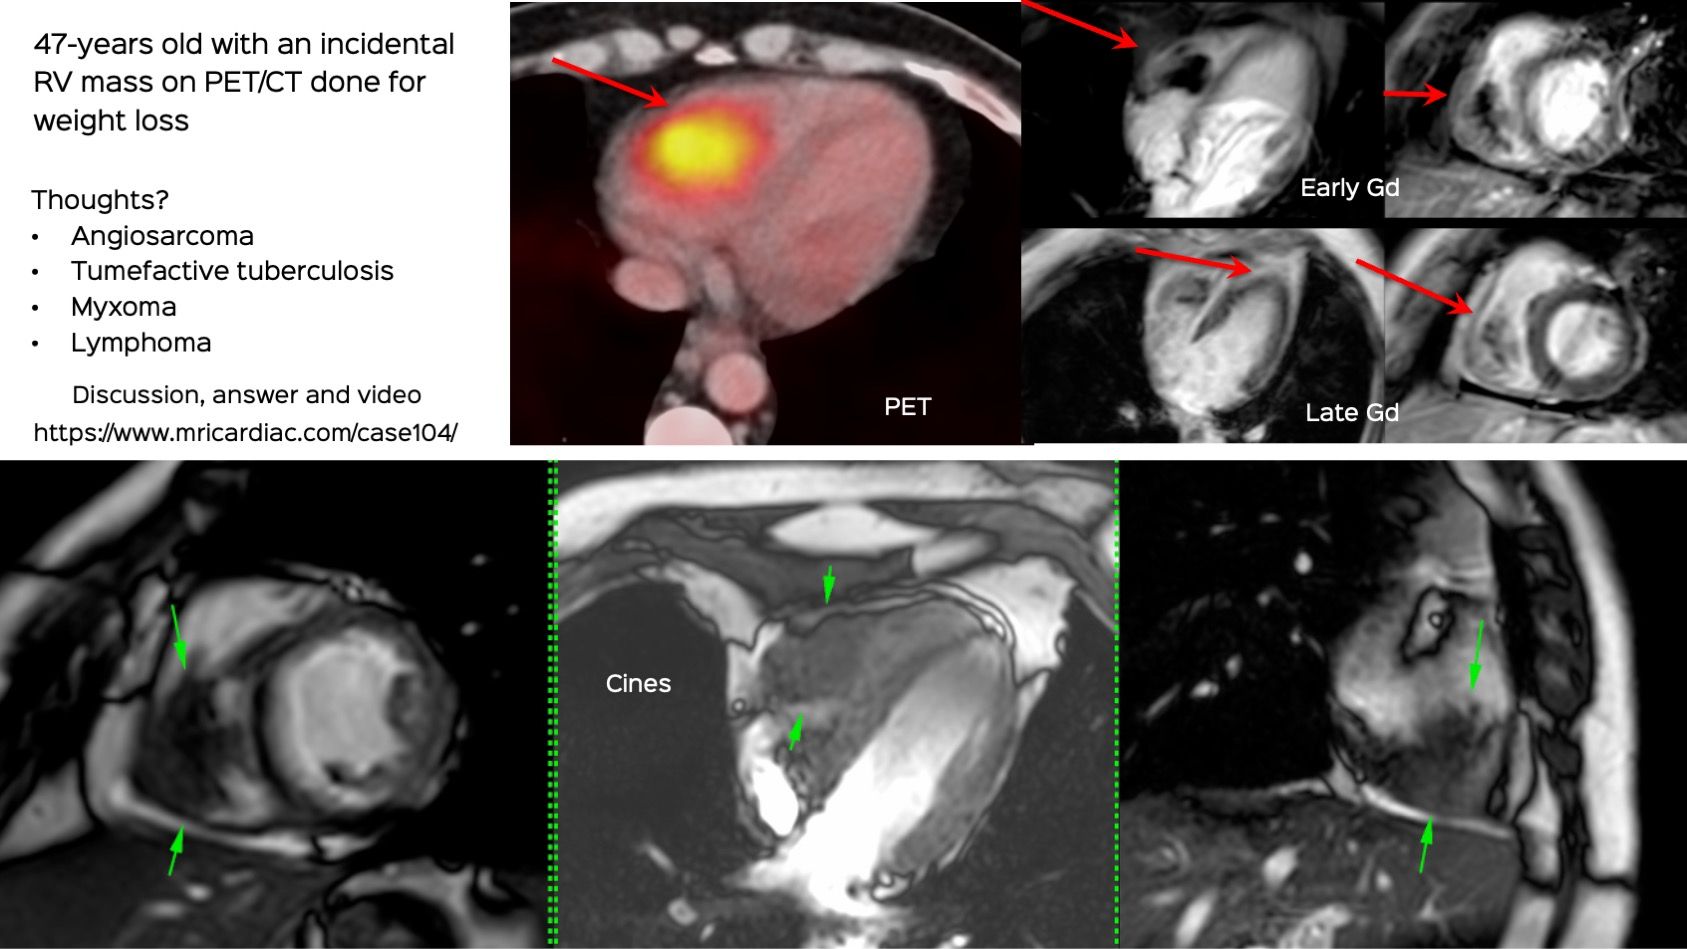

Case 104: The RV Mass Conundrum

RA and RV tumors have a typical differential diagnosis and have to be aggressively evaluated for etiology

This 47-years old man was found to have a mass on a PET/CT done for weight loss, in the right ventricle.

What do you think the diagnosis is?

The video discussed the case and the differentials and what the final outcome was.